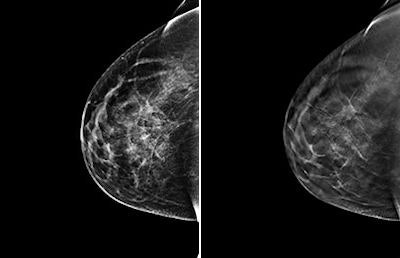

Left, 2D FFDM view of breast of 46-year-old woman. Right, 3D digital tomosynthesis view of breast. Images courtesy of Dr. Per Skaane, PhD.In fact, the combination of FFDM and tomosynthesis improved the cancer detection rate in women with a BI-RADS density measurement of 2, or minimal density, from 68% to 84% -- which could have interesting ramifications for clinical practice, according to Skaane.